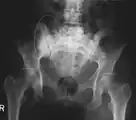

X-ray: Bone cancer in hip, spread from prostate cancer.

X-ray: Bone cancer in hip, spread from breast cancer.

CT scan: Parotid gland cancer spread to hip.